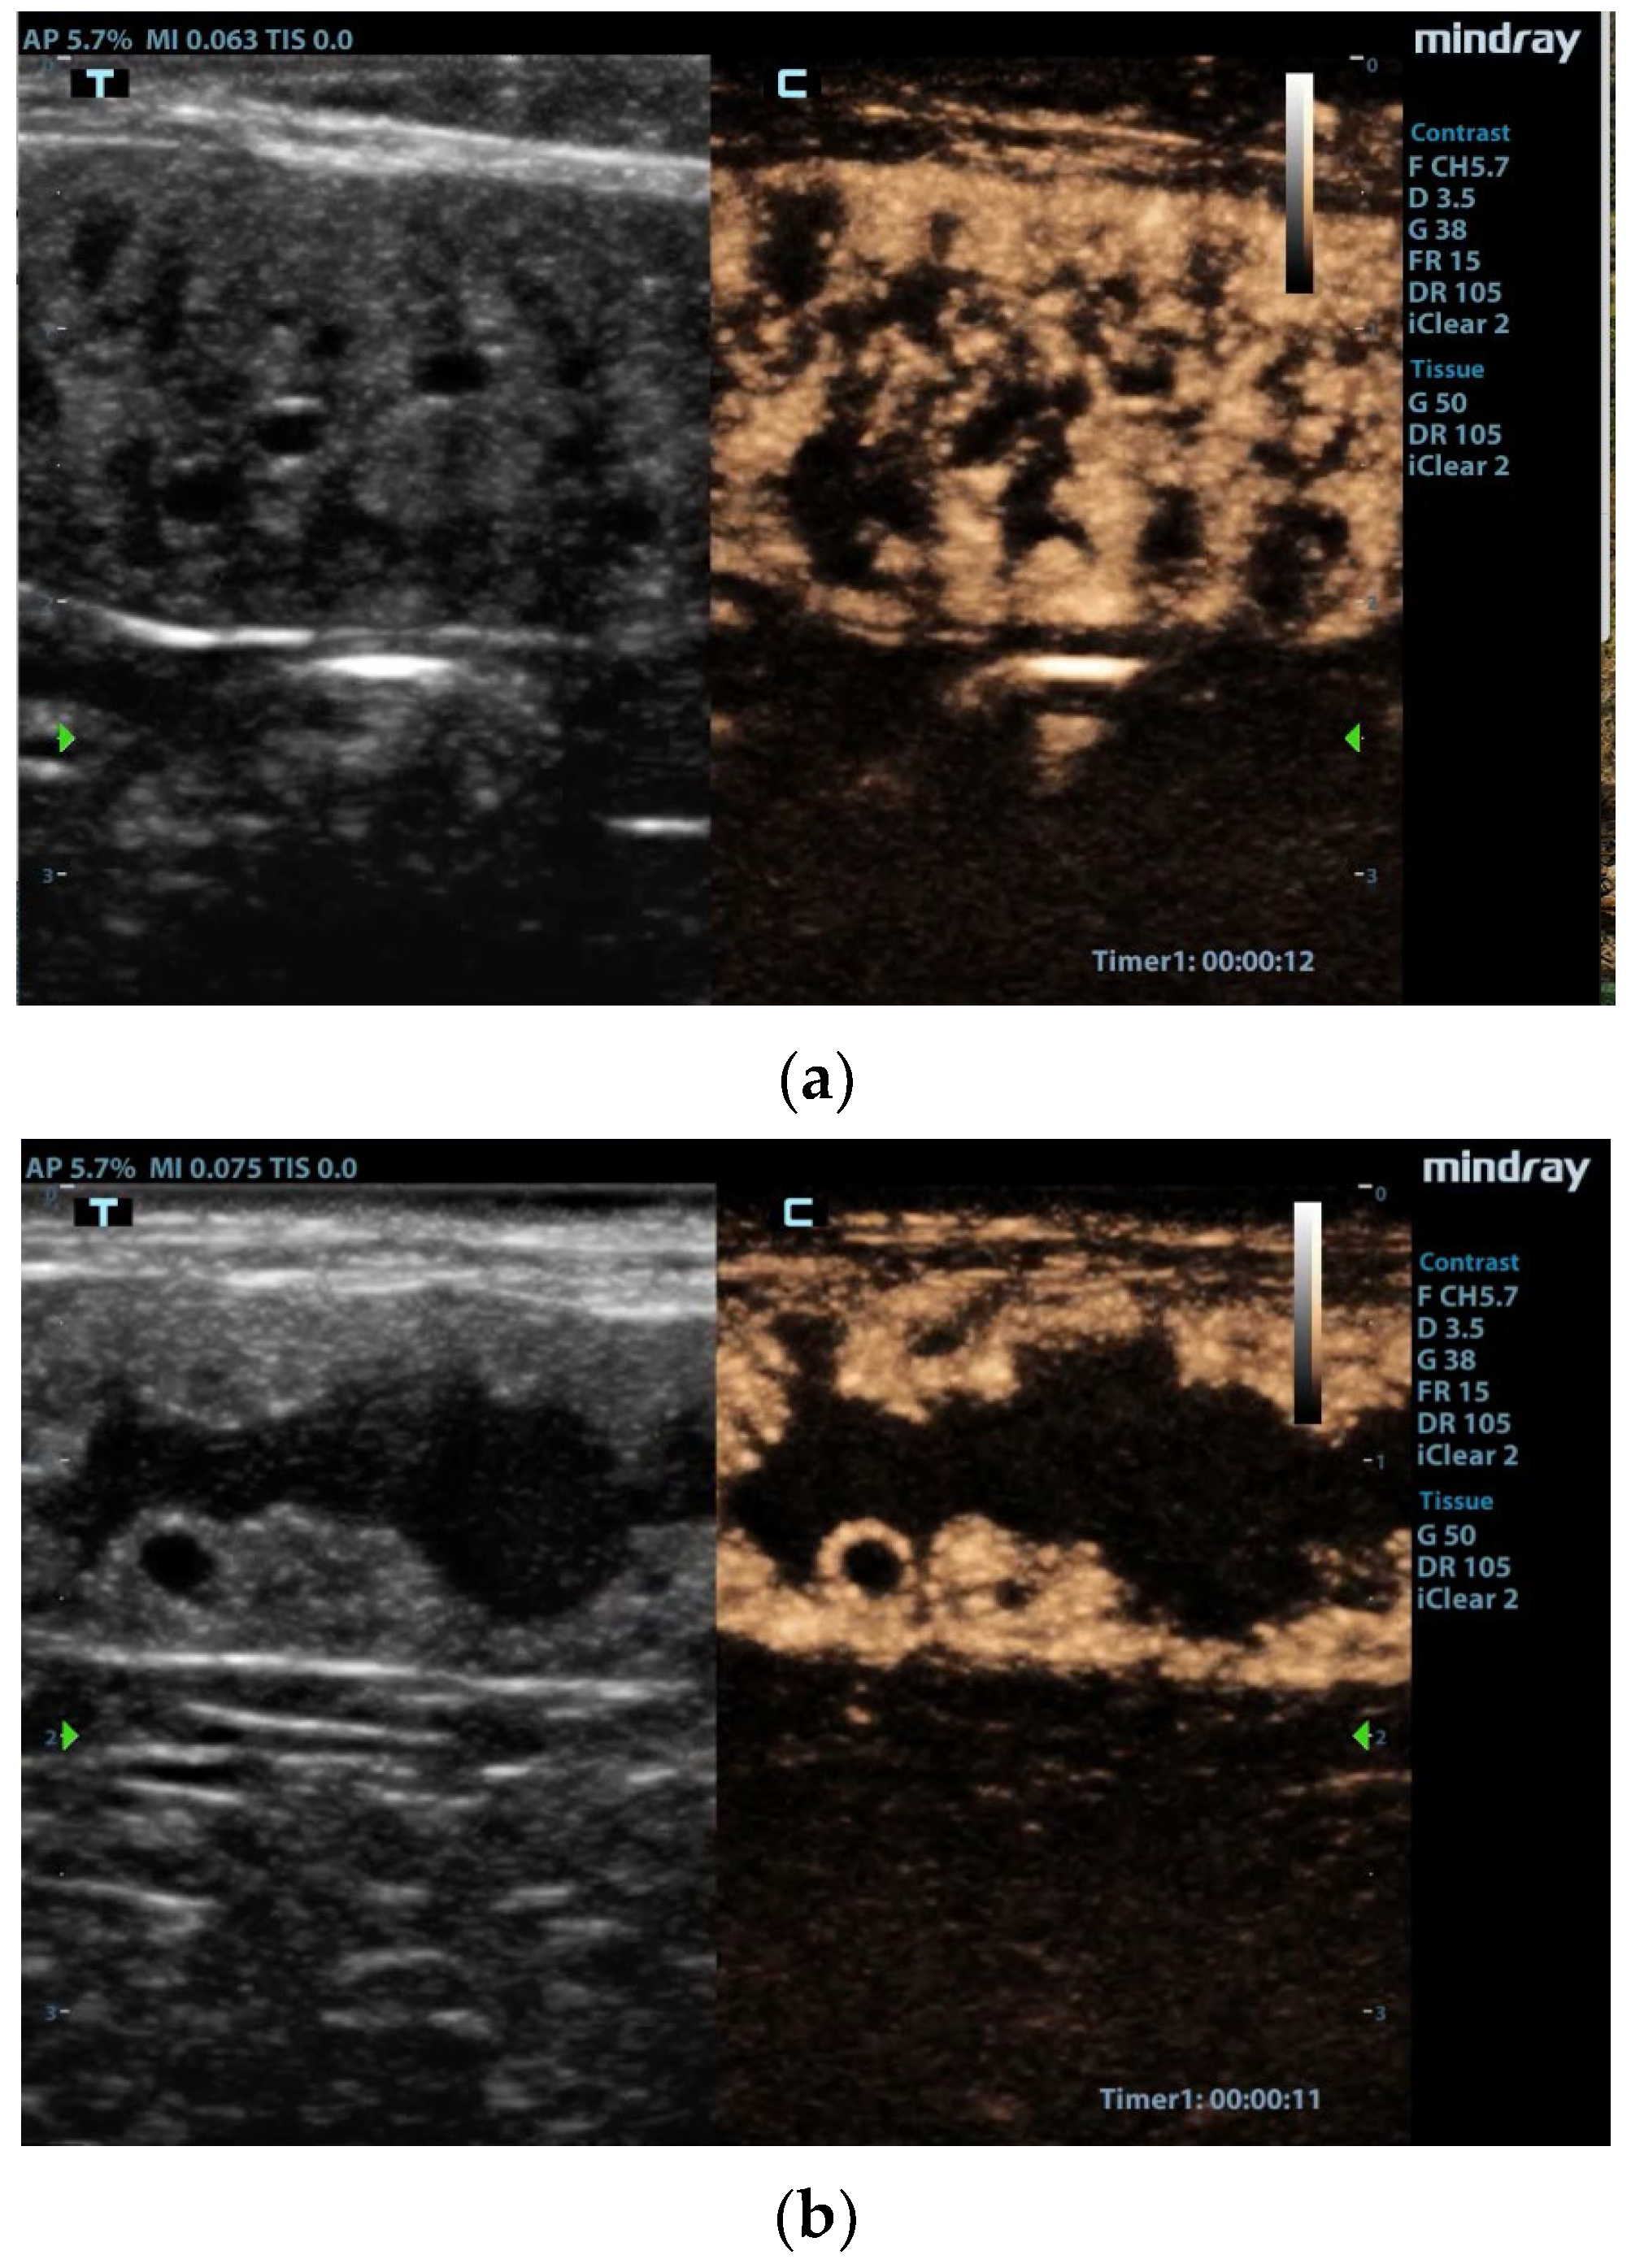

The authors performed qualitative and quantitative analyses of the contrast enhancement pattern and perfusion. From 6–8 s after contrast agent injection, the hyperplastic endometrium showed a homogeneous enhancement (wash-in phase), then the decrease in enhancement was slow during the wash-out phase, with evidence of contrast up to 2 min. The examination evidenced the opposition between the intense enhancement in the hyperplastic endometrium and the lack of signal inside the cysts (Figure 1). With regard to the vascular pattern, peripheral vessels were well represented, unlike vessels in the thin muscle layer, where only the small perpendicular ones were evident [42]. CEUS showed a rapid enhancement of endometrial proliferation in the uterus of all bitches correlated with an inflammatory condition, confirmed by a positive CD34 immunostaining in post-hysterectomy histological examination [42]. The CEUS investigation accurately highlighted the high number of vessels generated by the local angiogenesis, as demonstrated by immunohistochemical examination. Limitations of this work are the number of subjects and the inclusion criteria (high grade of CEH-pyometra) without a comparison with other grades of the pathology and other females evaluated during a non-pathologic diestrus phase [42].

Figure 1.

Contrast-enhanced images of the uterus [42]. (a) Enhancement of the hyperplastic endometrial layer with tortuous pattern due to presence of cysts and intraluminal material. (b) Uterine lumen filled with material, and very large cysts surrounded by vascularized tissue. Reproduced with permission from Quartuccio et al., Animals; published by MDPI, 2020 [42].